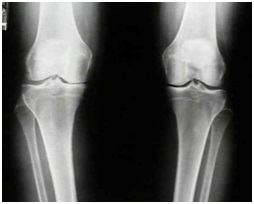

مفصل زانو بزرگترین مفصل بدن میباشد که محل اتصال سه استخوان ران ساق و کشکک میباشد.انتهای این استخوانها در محل ایجاد مفصل از غضروف پوشیده شده که سبب مهار ضربات وارد شده به مفصل میشود. مفصل زانو در ایستادن راه رفتن نشستن پریدن نقش دارد .

واژه آرتریت زمانی به کار میرود که مفصل دچار التهاب شده باشد و مفصل زانو بیشتر از تمام مفاصل بدن دچار آرتریت میگردد. آرتریت مفصل زانو در خانمها بیشتر اتفاق می افتد ودر افراد بالای پنجاه سال و چاق بیشتر است. در بیمارانی که مفصل زانو دچار آسیب شده است احتمال وقوع آرتریت بیشتر می باشد. وقوع آرتریت در مفصل زانو در افرادی که سابقه فامیلی این بیماری را دارند بیشتر است.

استئوآرتریت یا آرتروز زانو شایعترین نوع التهاب مفصل زانو(آرتریت) است. این بیماری در اثر فرسودگی و خراشیدگی غضروف مفصلی بوجود می آید و گاها کنده شدن قسمتی از غضروف به داخل مفصل وضعیت این بیماری را شدید تر مینماید. آرتروز با افزایش سن اتفاق می افتد وازمهمترین علل ناتوان کننده افراد مسن میباشد.

شایعترین علامت درد است .درد عمدتا با فعالیت تشدید میشود و معمولا به آرامی زیاد میشود اگر چه می تواند بصورت ناگهانی هم اتفاق بیفتد. در اثر آسیب به غضروف مفصلی ممکن است تورم گرمی مفصل یا احساس سفتی و خشکی در آن ایجاد شود. در شروع ایجاد این بیماری درد در بعضی مواقع ایجاد می شود و درسایر موارد بیمار بدون درد است. چندین سال پس از شروع این بیماری ممکن است تغییر شکل در مفصل زانو ایجاد شود.